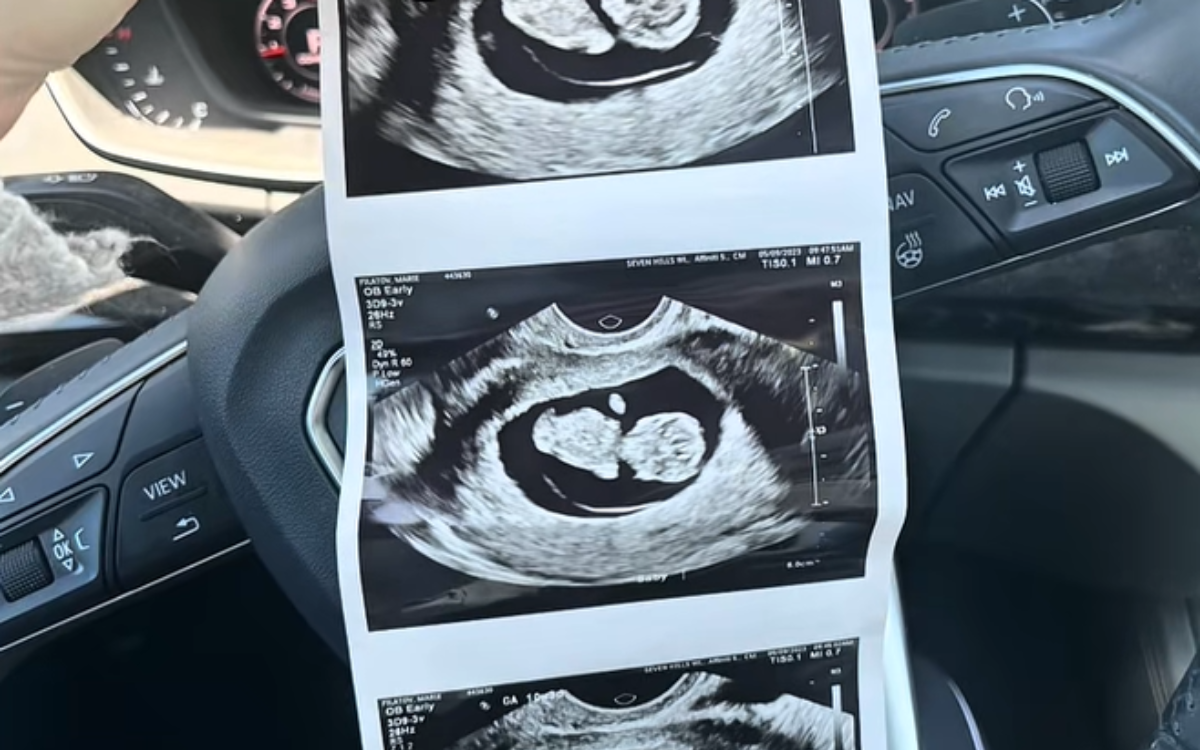

Pregnant Woman Goes For Ultrasound—‘Complete Shock’ At What Baby Is Missing

An Ohio woman, Marie Filatov, discovered during a routine ultrasound that her baby was missing a left hand. Her daughter, Myla, was born with a limb reduction defect but has thrived despite the condition. Filatov shared her story to celebrate Myla's achievements and to reassure other parents facing similar situations.

• During a routine 20-week ultrasound in 2022, doctors found her baby was missing a left hand.

• The baby, named Myla, was born with a limb reduction defect, affecting 1 in every 2,100 U.S. births.

• The suspected cause was a vascular event like a blood clot early in pregnancy.